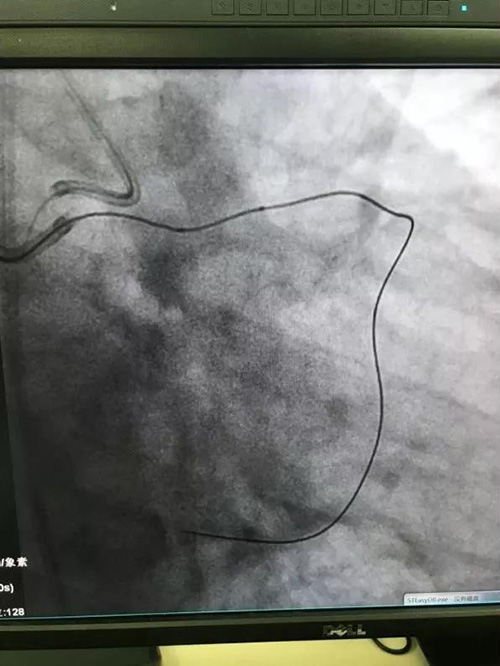

赵鹏医生在葛院士团队马剑英教授指导下进行手术操作学习,特别是CTO逆向开通技术。逆向技术是指通过对侧或同侧侧支循环血管所形成的交通血管,或经过外科搭桥术后的桥血管进入闭塞病变远端, 应用微创导丝从堵塞血管的两段夹击打通病变处,进行犯罪病变的介入治疗。

CTO逆向开通技术